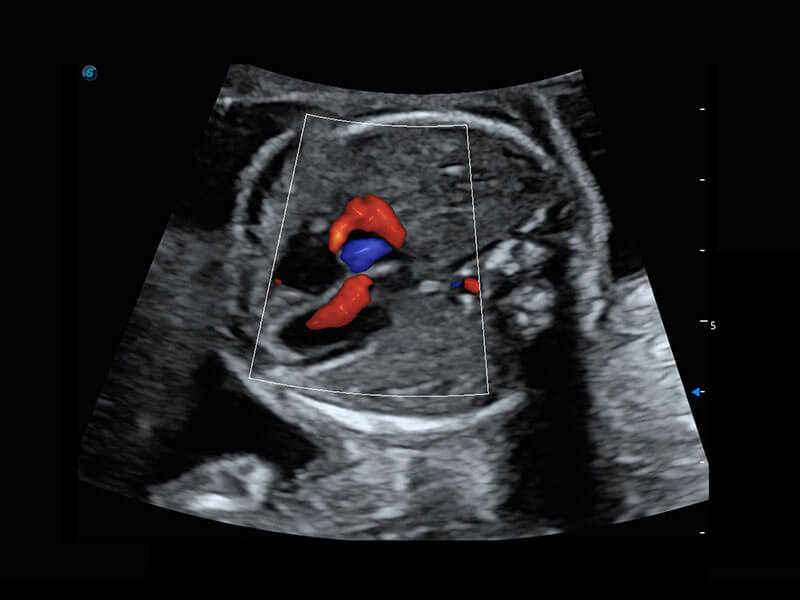

胎心筛查

P60搭载一系列胎儿心脏成像技术,实现精细的胎儿心脏评估。

• 右室双出口

• 胎心容积成像